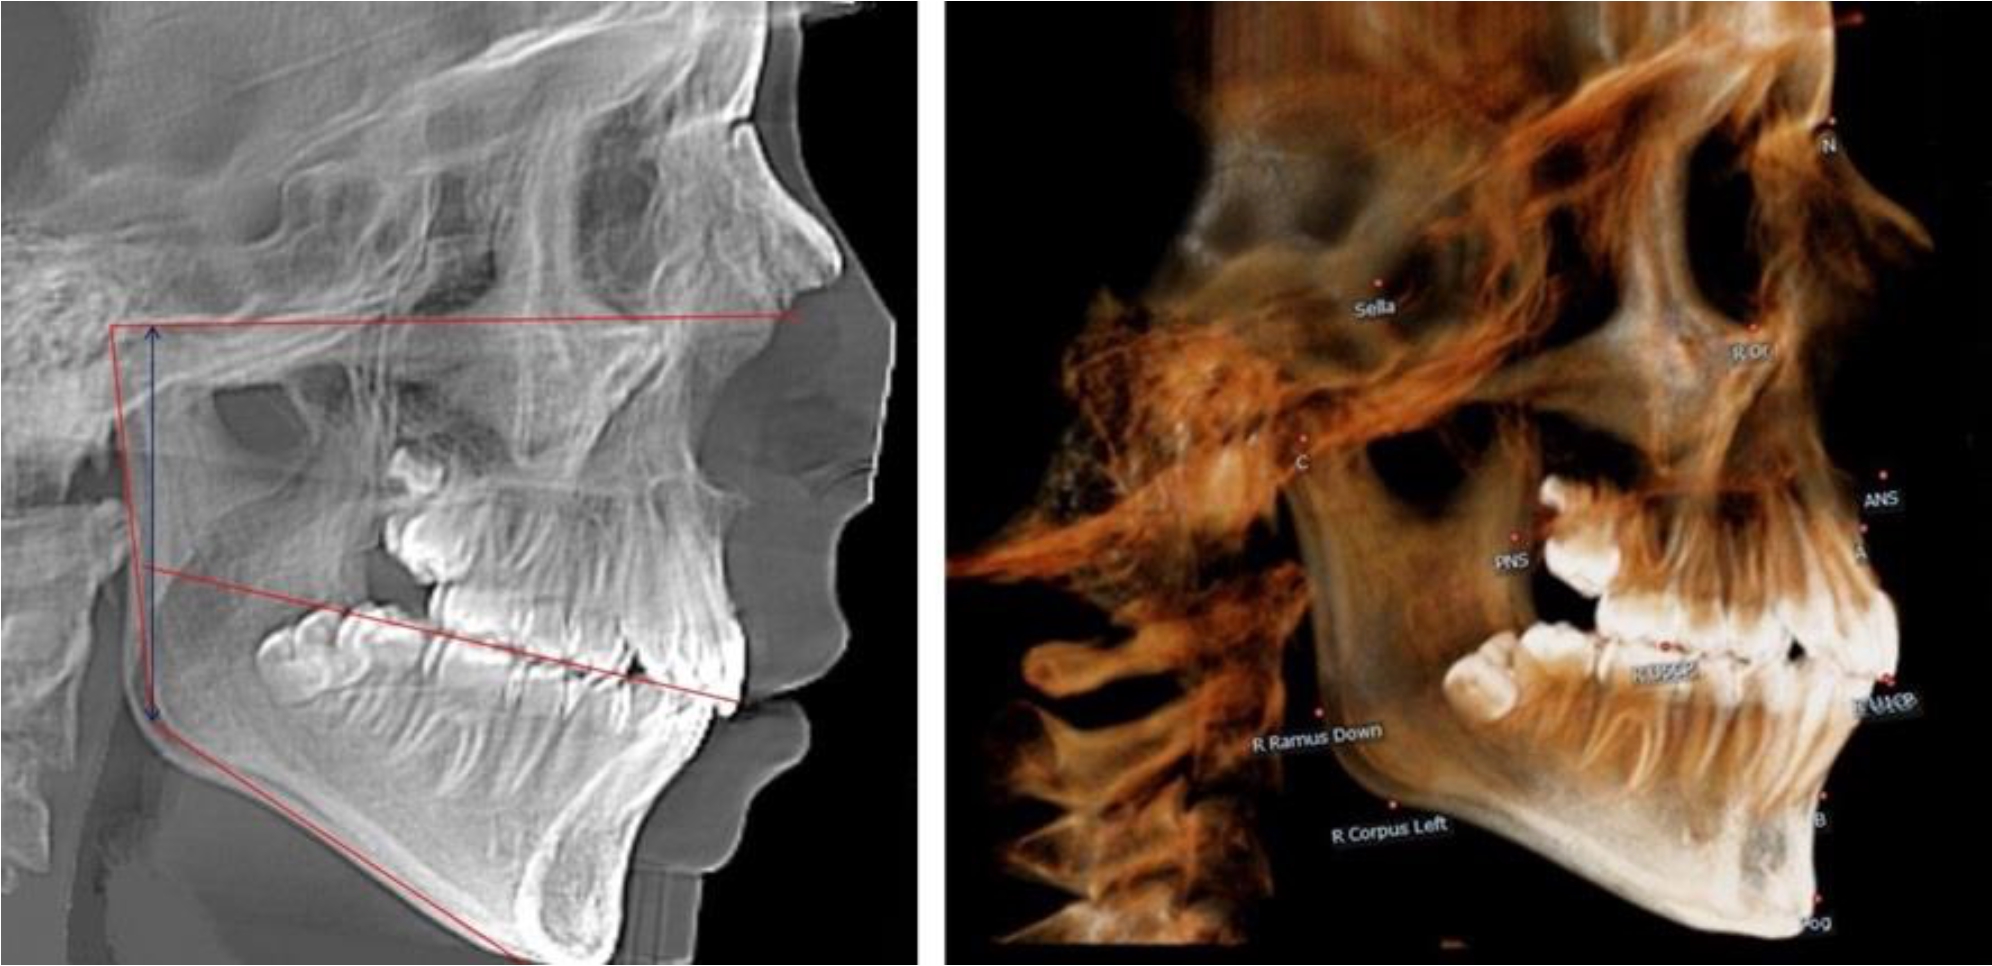

В 3-й группе были проанализированы 9 телерентгенограмм и 9 ортопантомограмм, что составило (8,49 ± 2,71) % от числа изученных рентгенограмм (рис. 3).

Рис. 3. ТРГ и ОПТГ пациента после смены молочных резцов

На всех рентгенограммах произошла смена молочных резцов постоянными. Окклюзионная линия делила ветвь на два отдела.

Высота ветви у детей у детей 3-й группы составляла (51,07 ± 2,72) мм, что было достоверно больше, чем у детей 1-й группы (р ˂ 0,05). При этом высота верхней окклюзионно-суставной части была (29,06 ± 1,44) мм, а нижней – (22,01 ± 1,59) мм. Высота верхней части была больше нижней, что и определяло особенности соразмерности частей ветви нижней челюсти в анализируемый возрастной период.

Относительные показатели соразмерности частей ветви нижней челюсти показали, что отношение высоты верхней части ветви к нижней в среднем составляло 1,32 ± 0,14. Отношение общей высоты ветви к верхней ее части составляло 1,75 ± 0,12, а отношение общей высоты ветви к нижней ее части было 2,32 ± 0,17, что и определяло особенности соразмерности частей ветви нижней челюсти в анализируемый возрастной период.

В 4-й группе были проанализированы 12 комплектов рентгенограмм, что составило (11,32 ± 3,08) % от общего числа. На всех рентгенограммах произошла полная смена всех молочных зубов постоянными. Окклюзионная линия делила ветвь на два отдела (рис. 4).

Рис. 4. ТРГ пациента после смены всех молочных резцов

Высота ветви у детей 4-й группы составляла (54,27 ± 2,59) мм, что было достоверно больше, чем у детей 1-й группы (р ˂ 0,05). При этом высота верхней окклюзионно-суставной части была (32,51 ± 1,72) мм, а нижней – (21,76 ± 1,42) мм. Высота верхней части была больше нижней, что и определяло особенности соразмерности частей ветви нижней челюсти в анализируемый возрастной период.

Относительные показатели соразмерности частей ветви нижней челюсти показали, что отношение высоты верхней части ветви к нижней в среднем составляло 1,49 ± 0,12. Отношение общей высоты ветви к верхней ее части составляло 1,67 ± 0,14, а отношение общей высоты ветви к нижней ее части было 2,49 ± 0,15, что и определяло особенности соразмерности частей ветви нижней челюсти в анализируемый возрастной период.